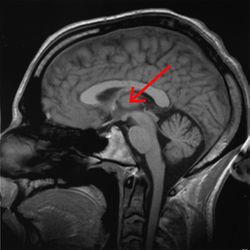

مقطع صورة رنين مغناطيسي لمخ بشري, المهاد مبين فيه. | ||